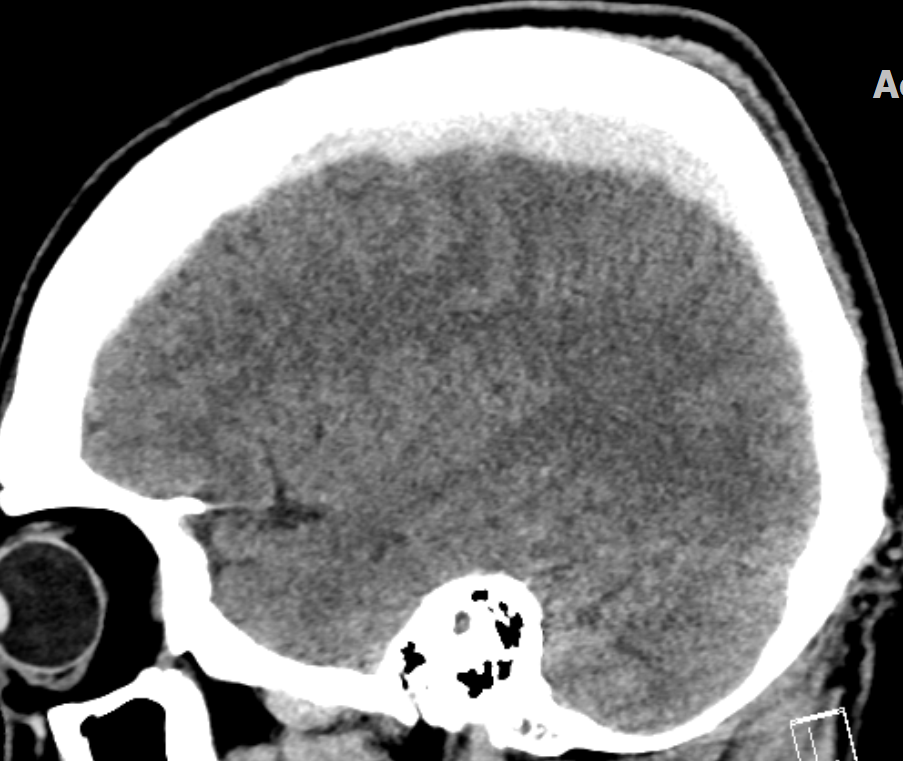

4.파열된 정맥에서 혈액이 경막하강에 고여 CT 상 반월상 형태로 나타남.

6.혈종이 지속적으로 증가하면 뇌 구조물이 반대편으로 밀리는 Midline shifting이 발생하며, 이는 중증 신경학적 손상의 지표로 간주함.

심한 경우 uncal herniation 또는 transtentorial herniation 으로 진행할 수 있다.